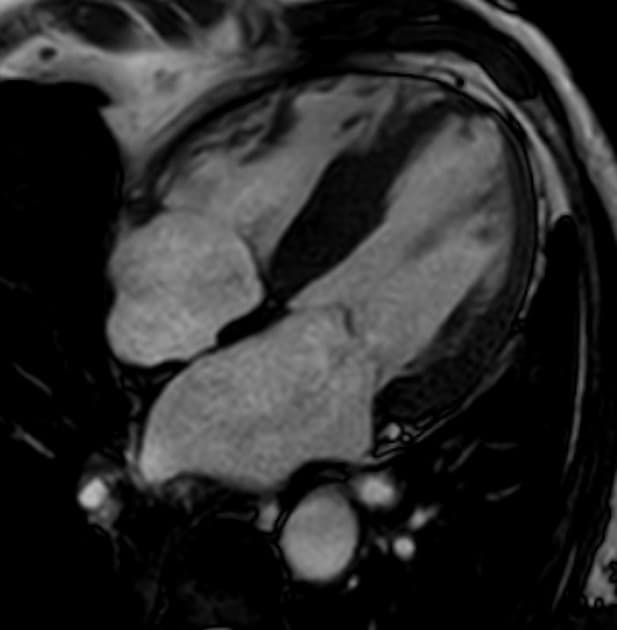

Tim

- Thấy hình ảnh phì đại cơ tim rõ rệt ở thành bên trái thất trái, với sự dày cơ tâm thất đáng kể tại đỉnh tim và hẹp đáng kể trong thì tâm thu.

Bệnh cơ tim phì đại đỉnh không tắc nghẽn (apical non-obstructive hypertrophic cardiomyopathy - Yamaguchi hypertrophy)

- "Bệnh cơ tim phì đại đỉnh, hay hội chứng Yamaguchi, là một dạng biến thể của bệnh cơ tim phì đại, đặc trưng bởi tình trạng phì đại riêng biệt ở đỉnh thất trái."

Bệnh cơ tim phì đại đỉnh không tắc nghẽn, còn gọi là hội chứng Yamaguchi, là một dạng biến thể hình thái của bệnh cơ tim phì đại, chủ yếu ảnh hưởng đến đỉnh thất trái mà không có tắc nghẽn đoạn ra thất trái. Bệnh lần đầu được mô tả ở Nhật Bản và phổ biến hơn ở các quần thể châu Á. Các phương tiện hình ảnh như siêu âm tim và cộng hưởng từ tim cho thấy hình ảnh dày thành đỉnh rõ rệt, thường có hình dạng giống 'cái xẻng' ở thất trái trong thì tâm trương. Mặc dù không tắc nghẽn, bệnh nhân vẫn có thể gặp các triệu chứng như đau ngực, khó thở hoặc rối loạn nhịp do rối loạn chức năng tâm trương hoặc thiếu máu vi mạch. Dấu hiệu điện tâm đồ đặc trưng là sóng T âm lớn ở các chuyển đạo trước tim giúp phân biệt với các nguyên nhân khác gây phì đại đỉnh hoặc bệnh tim thiếu máu cục bộ. Tiên lượng dài hạn thường thuận lợi, nhưng nguy cơ đột tử do tim, dù hiếm, vẫn cần được theo dõi.